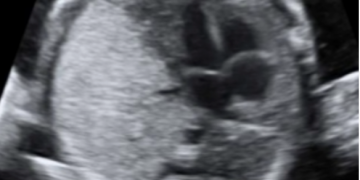

Guida al Counselling di Ottobre 2022: ridotta riserva ovarica e CFA

Cari colleghi, vi presentiamo la guida al counseling di Ottobre relativa alla ridotta riserva ovarica e alla conta dei follicoli antrali!! Potrete scaricarla cliccando sul link. Grazie a Carlotta Zorzi...